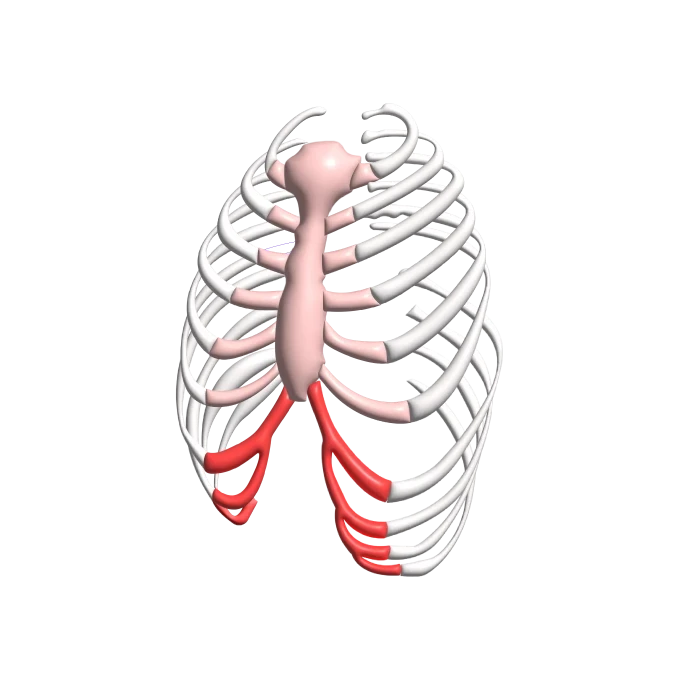

From sshi.ie

RIB FLARE SSHI Flared Ribs After Nuss Procedure It seems my belly is protruding out. I had nuss procedure in 2016 and after 2.5+ years the bar was removed. Whether it's due to posture, muscle imbalances, or something else, i'll guide you through the most effective strategies to correct it. The aesthetic effects after corrective rib cage surgery using the nuss procedure are quite satisfactory. They are pretty. Flared Ribs After Nuss Procedure.

RIB FLARE SSHI Flared Ribs After Nuss Procedure I had nuss procedure in 2016 and after 2.5+ years the bar was removed. Because more adults are undergoing pectus repair with the nuss procedure, an understanding of a potentially increased risk is necessary. In this blog post, you'll learn what causes flared ribs, how to identify them, and the best exercises and tips to correct them. Whether it's due. Flared Ribs After Nuss Procedure.